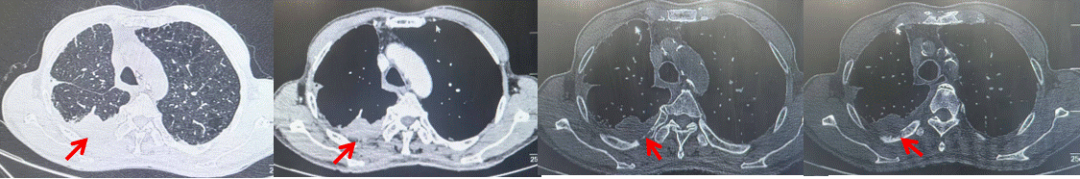

2024.11.19患者出现右侧胸痛,复查胸部CT检查示右侧胸膜肿物,大小约31mmX24mm,右侧4、5肋骨骨质破坏,考虑转移(如图2)。建议患者穿刺活检取病理明确诊断,患者拒绝,经MDT会诊后结合影像学表现及病史考虑为胸膜转移,肋骨转移,分期为rT0N0M1a IVA期,DFS仅仅17个月。2024.12.05起行信迪利单抗联合培美曲塞+卡铂方案治疗4周期,复查胸CT评效PR(如图3)。之后给予信迪利单抗+培美曲塞维持治疗6周期,期间复查CT评效PR(如图3)。目前信迪利单抗+培美曲塞维持治疗中,截止至目前PFS约为8个月,治疗期间未出现明显毒副反应。

图2:患者胸膜及肋骨转移(2024.11)胸部CT肺窗、纵隔窗及骨窗

图3:患者免疫联合化疗治疗后胸部CT,(A、B)图展示信迪利单抗联合培美曲塞+卡铂治疗

4周期(2025.02)疗效,(C、D)图展示信迪利单抗+培美曲塞维持治疗6周期(2025.07)疗效